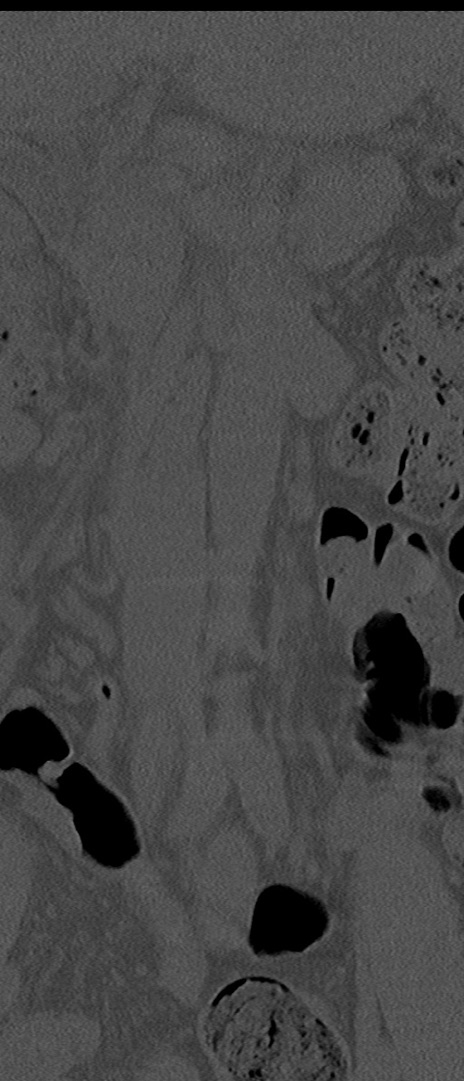

腰椎CT